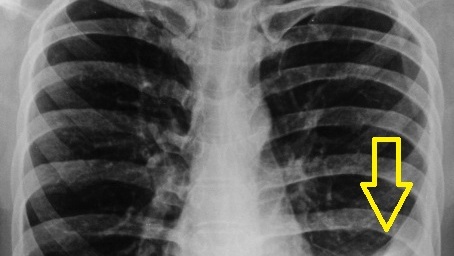

Плеврит – это воспаление плевры (серозной оболочки, покрывающей легкие и выстилающей грудную полость), которое может сопровождаться накоплением жидкости (экссудативный плеврит) или протекать без выпота (сухой плеврит).  - Острая боль в боку, усиливающаяся при дыхании и кашле. - Сухой кашель. - Шум трения плевры при аускультации. - Тупые боли, чувство тяжести в груди. - Одышка (из-за сдавления легкого жидкостью). - Притупление перкуторного звука, ослабление дыхания на пораженной стороне.  - Рентген/КТ грудной клетки — выявление уровня жидкости...